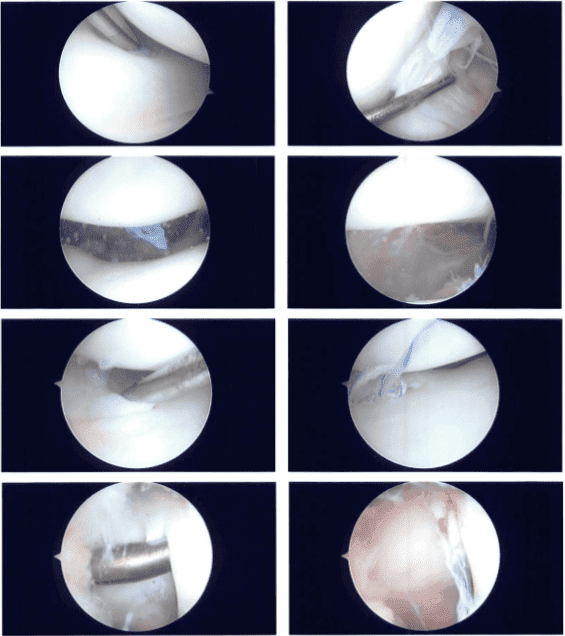

Se introdujo un artroscopio a través de un orificio lateral de entrada. La aguja espinal se utilizó para crear el portal de entrada medial. Se examinó el menisco medial y se encontró una rotura periférica a lo largo del cuerpo del menisco.

No hubo lesión en el cartílago. Se encontró que el LCA estaba intacto cuando se examinó la muesca intercondilar. Durante un examen del compartimento tibiofemoral lateral se descubrió deshilachamiento del cuerno posterior del menisco lateral.

El cartílago no resultó dañado. Se encontró que el compartimento patelofemoral tenía cartílago completo. Se eligió para reparar la rotura del menisco medial. El desgarro se preparó con un raspado y una afeitadora, y se introdujeron un FasT-Fix y una artroscopia a través del portal lateral y el portal medial, respectivamente.

Se colocó un suturón horizontal para colchón y luego se cortó. La fijación tuvo éxito. Se tomaron y conservaron fotografías. También se afeitó el menisco lateral posterior y se tomaron y almacenaron fotografías.

Se usaron picos de condroplastia, así como cuatro microfracturas, para permitir la ventilación de médula ósea. Se podían observar glóbulos de grasa, seguidos de sangre, ventilando por los orificios para ayudar a que el menisco se curara más rápido. Las fotografías finales fueron tomadas y conservadas. La rodilla había sido completamente irrigada y drenada.

Imágenes intraoperatorias